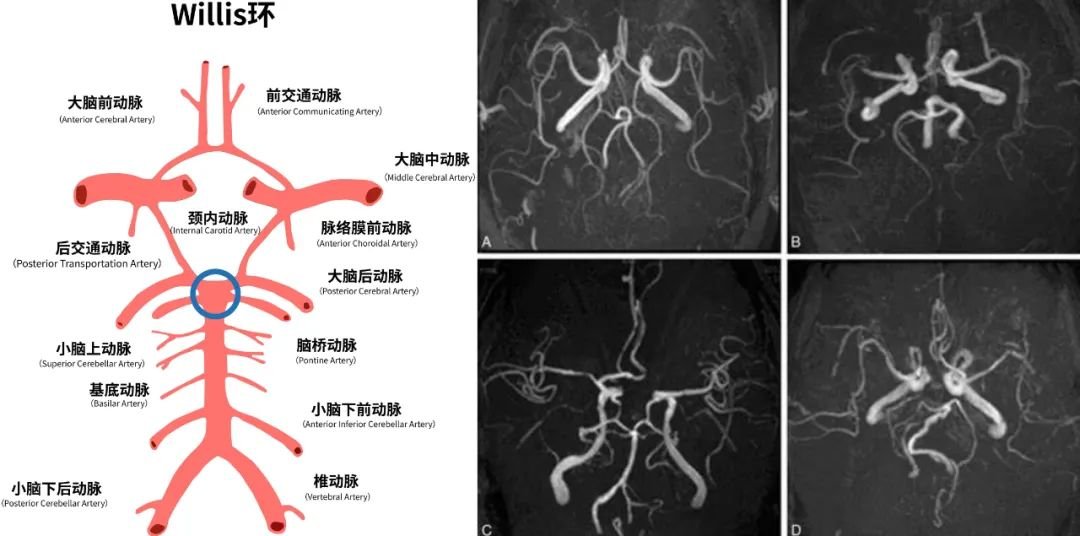

虽然有一些颅咽管瘤镜下一看确实难度很大,黏连严重,不止是和它起源的部位,甚至跟周围的血管,因为它整个颅咽管瘤起源的地方,还有一个叫做Willis环的结构,它就像闪亮红星一样,散散发光,特别耀眼。

它又被称为大脑动脉环,是指供应脑组织的动脉在脑底形成的环状结构。它是颅内较重要的侧支循环途径,将双侧大脑半球和前、后循环联系起来。

有些颅咽管瘤会跟这些血管粘的都很紧,然后周围的这些视神经、动眼神经,还有一些下丘脑垂体柄垂体相关结构,有时候粘的是严重的。